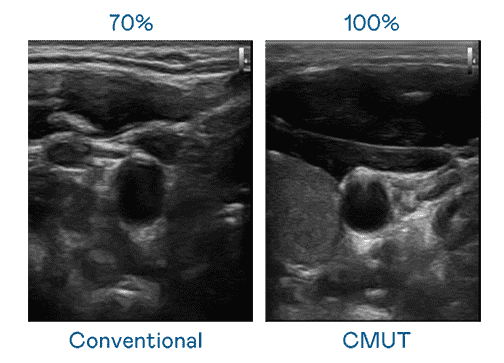

CMUT 技术是一种用电容式微机电元件来产生超音波讯号的技术。。。。与传统 PZT 压电式技术相比,,,,CMUT 频宽增加 30%,,,更宽频的超音波讯号让影像解析度大幅提升,,,,是实现高影像品质医疗超音波扫描、、促进精准医疗发展的关键技术。。

大频宽带来超清晰影像

超音波影像的解析度高低,,,,首先取决于探头能发出的讯号频宽。。。z6mg·人生就是博 CMUT 可提供高清晰的超音波讯号,,,,提供高频宽、、、、高灵敏度、、、、影像纹理细节更高的超音波影像,,协助医护人员缩短影像判读时间及利用精准的医疗影像进行诊断。。。